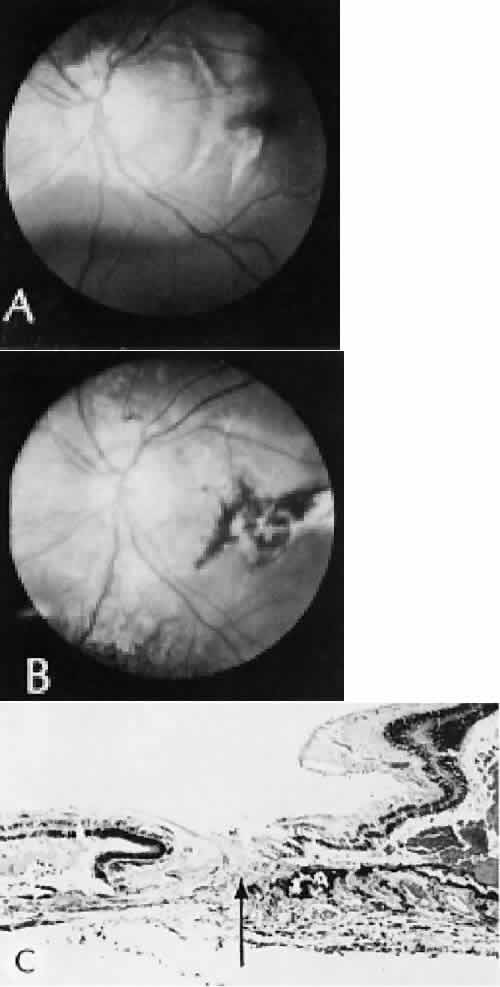

| Successful wound healing in the eye is a precise, ordered series of events